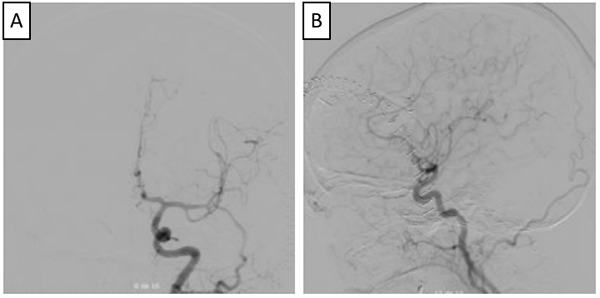

Figura 3

. Arteriografía de control postoperatoria (A y B), en la que se observa adecuada exclusión de aneurisma cerebral